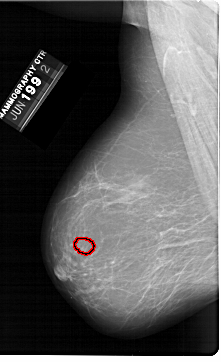

A_1398_1.LEFT_MLO

LEFT_MLO LINES 6871 PIXELS_PER_LINE 4186 BITS_PER_PIXEL 12 RESOLUTION 43.5 OVERLAY

FILE: A_1398_1.LEFT_MLO.OVERLAY

TOTAL_ABNORMALITIES 1

ABNORMALITY 1

LESION_TYPE MASS SHAPE LOBULATED MARGINS CIRCUMSCRIBED

ASSESSMENT 3

SUBTLETY 3

PATHOLOGY BENIGN

TOTAL_OUTLINES 1

BOUNDARY